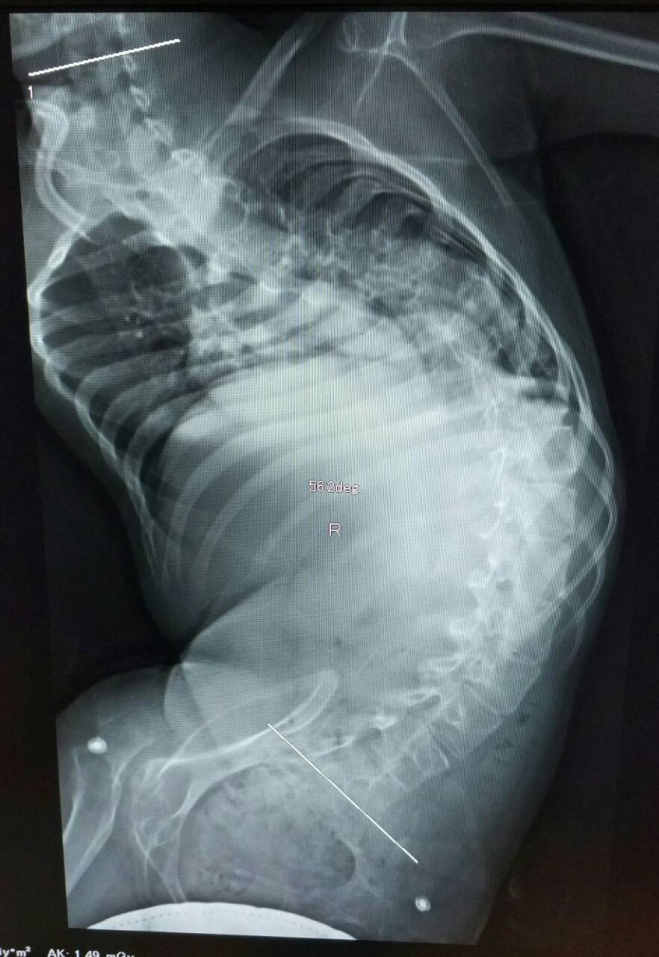

К 2009 году у меня начались первые проблемы со спиной. Сначала я начал сутулиться, а потом, понемногу, позвоночник стал уходить вбок. Мама обратилась к врачам-ортопедам, и, мне посоветовали носить корсет. Так как, в г. Кишинева невозможно изготовить необходимый мне корсет, мы стали искать, где можно его изготовить. Таким образом, в 2009 году, мама вышла на общество «детей СМА» из г. Харькова, Украина, и они помогли нам связаться с врачом из Украинского научно-исследовательского института протезирования, протезостроительства и восстановления работоспособности из г. Харькова. И, по необходимости, в данном институте мне стали изготавливать корректирующие корсеты, проводя параллельно курсы реабилитации.

И так, в течение 10 лет мне периодически делают корсеты, благодаря которым поначалу я могу сидеть ровно хоть какое-то время. Мог заниматься с учителями и делать уроки. Благодаря тому, что в корсете спина становится ровнее, у меня увеличивается объем движений. Однако корсет не решил проблему со сколиозом. Лишь добавил сложностей и болячек. Проблема в том, что корсет сильно давит, стирает кожу до кровавых ран, которые просто не заживают. А также постоянно на спине остаются синяки и большие гематомы. У меня даже есть участки кожи, к которым больно прикасаться, это все от того, что корсет сжимает. Особенно тяжело становится тогда, когда уже необходима замена корсета, но у нас нет возможности сразу его заменить.

Из-за сильного сколиоза, я могу смотреть только в одну сторону, так как повернуть шею/корпус вправо практически невозможно. Поэтому я вижу только то, что доступно мне с левой стороны. Также, в корсете очень тяжело гулять. Так как сидеть в коляске я могу только в корсете, то гуляю я очень редко, ведь выйти одетым сразу в корсет очень сложно. А летом в корсете невыносимо жарко, так как пластик не дает дышать и покрывает всю грудь и спину.

Живу я с мамой и сестрой. Папа ушел от нас, когда мне было еще три года. Но, он помогает, возит меня на тренировки по плаванью и на занятия по иппотерапии. Очень люблю животных, особенно лошадей и собак. Но, из-за проблем с позвоночником, мне с каждым днем становиться все тяжелее и тяжелее заниматься. Корсеты, которые мне изготавливают в Харькове – уже не держат мою спину, и не помогают в ее коррекции. Когда я устаю, у меня очень болят мышцы и мне тяжело дышать. Очень сильно болит вся спина, боль настолько сильная, что ее не описать. Операция по коррекции позвоночника – мой шанс на улучшение моей жизни. Проблема ведь не только в том, что я устаю сидеть, а и в том, что часть внутренних органов деформируется из-за неправильной осанки, что влечет за собой другие проблемы со здоровьем, такие как больные легкие, тазобедренные суставы, а самое главное сердце. Такой сколиоз может сдавить самый важный орган легкие, и может случится беда… можно просто задохнуться. Что бы этого избежать, нужно выпрямить кривой позвоночник. А это можно сделать только с помощью операции.

О клинике доктора Бакланова мы узнали случайно. Мама просматривала ленту в инстаграме и увидела пост девочки из г.Уфа, которая собирала деньги, чтобы поехать в клинику Доктора Бакланова на операцию. По фотографии было видно, что у девочки схожий с моим диагноз. Мы заинтересовались и нашли ваш клинику. Так мы решили попробовать связаться, а вдруг и у меня есть шанс на операцию. Связались с клиникой, получили консультацию доктора, по обследованиям, которые были нам назначены. Я ждал консультации врача. Верил и надеялся, что он не откажется от меня. Взвесив все за и против, подтвердив сложный сколиоз и сам диагноз. Доктор сказал, что возможно провести операцию! Я был счастлив от этих слов!!! Теперь я знаю где мне могут помочь и спасти жизнь. Теперь моя самая заветная места сделать операцию и выровнять позвоночник. Ведь тогда всего остального я достигну!

Я понимаю, что я гражданин другого государства. Но, в нашей стране нет возможности проведения, даже близких к таким, операции. Центр патологии позвоночника и нейрохирургии доктора Бакланова – это мой единственный шанс на спасение и нормальную жизнь, где у меня есть будущее. Я переживал и был очень рад, когда узнал, что по результатам анализов и консультации, Андрей Николаевич Бакланов сказал, что готов взять меня на операцию. К сожалению, несмотря на то, что и мама, и сестра работают, самостоятельно оплатить операцию и необходимое лечение у нас нет возможности. Я Вас очень прошу помочь мне оплатить имплант, его стоимость 809 400 руб. Помогите пожалуйста, вся надежда на ваш фонд и поддержку добрых людей. Я очень хочу жить!